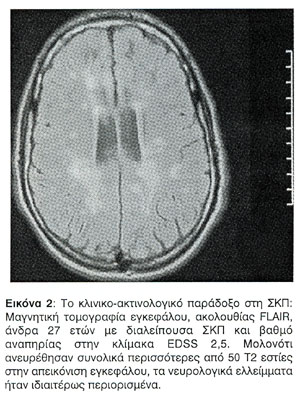

Η συσχέτιση του βαθμού αναπηρίας, όπως αυτός προσδιορίζεται από την κλίμακα EDSS, με τη βαρύτητα των βλαβών στη συμβατική μαγνητική τομογραφία έχει βρεθεί να είναι χαμηλή27,28, έως οριακή29. Η περιγραφείσα δυσαρμονία μεταξύ του φορτίου των βλαβών στη συμβατική μαγνητική τομογραφία και της κλινικής εικόνας αποτελούν την πρώτη όψη του "κλινικο-ακτινολογικού παραδόξου" της ΣΚΠ (Εικόνα 1, Εικόνα 2). Η δεύτερη όψη του παραδόξου, όπως έχει ήδη περιγραφεί, αφορά στους ασθενείς που εμφανίζουν βλάβες σε οξεία φάση στη μαγνητική τομογραφία χωρίς συνοδό κλινική έξαρση της νόσου. Η τρίτη όψη αφορά στους ασθενείς με πρωτοπαθώς προϊούσα ΣΚΠ. Στις περιπτώσεις αυτές η ανεύρεση ολιγάριθμων βλαβών στη μαγνητική τομογραφία, παρά τη μεγάλη κλινική αναπηρία, αποτελεί συνήθως τον κανόνα (Εικόνα 3).

Ασθενείς με πρωτοπαθώς προϊούσα ΣΚΠ εμφανίζουν χαμηλότερο αριθμό και όγκο βλαβών στην Τ2 ακολουθία της μαγνητικής τομογραφίας εγκεφάλου απ' ότι ασθενείς με διαλείπουσα ή δευτεροπαθώς προϊούσα ΣΚΠ13. Αυτό συμβαίνει παρά τη συγκριτικά μεγαλύτερη αναπηρία των ασθενών αυτών. Η παρατήρηση αυτή αποτελεί μια από τις όψεις του "κλινικο-ακτινολογικού παραδόξου" στη ΣΚΠ. Επίσης, στην πρωτοπαθώς προϊούσα ΣΚΠ οι βλάβες σπάνια προσλαμβάνουν σκιαγραφικό14. Σημειώνεται ότι δεν παρατηρείται σημαντικά μεγαλύτερος αριθμός και όγκος μυελικών βλαβών σε ασθενείς με πρωτοπαθώς προϊούσα ΣΚΠ15.